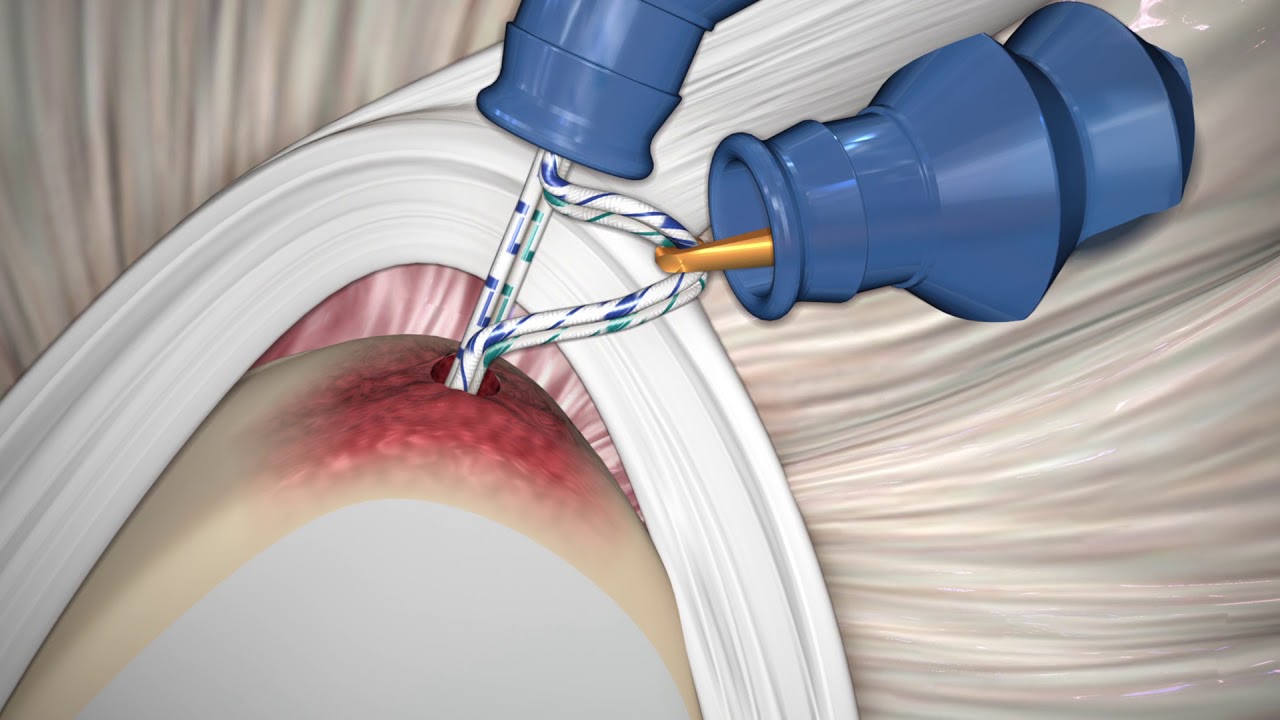

Reconstrucción ligamentos cruzados de rodilla por artroscopia

La Artroscopia de Rodilla;es una Técnica mínima invasiva,la cual consiste en realizar insiciones de 1cm, para introducir una cámara y visualizar la articulación en su totalidad, ademas de introducir instrumental para limpieza con agua estéril y asi poder realizar: reparación con sutura meniscal, reconstrucción de Ligamentos cruzados con técnica all inside con solo 4 incisiones de 1cm,Auto trasplante de cartílago, técnica la cual disminuye el indice de dolor y es ambulatoria , con tiempo de recuperación menor a las actividades cotidianas.